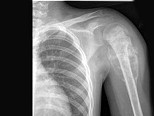

- 单项选择题男,28岁, 右上臂肿胀、疼痛,结合图像, 最可能的诊断是 ( )

A、骨肉瘤

B、成骨性骨转移瘤

C、化脓性骨髓炎

D、滑膜肉瘤

E、骨巨细胞瘤